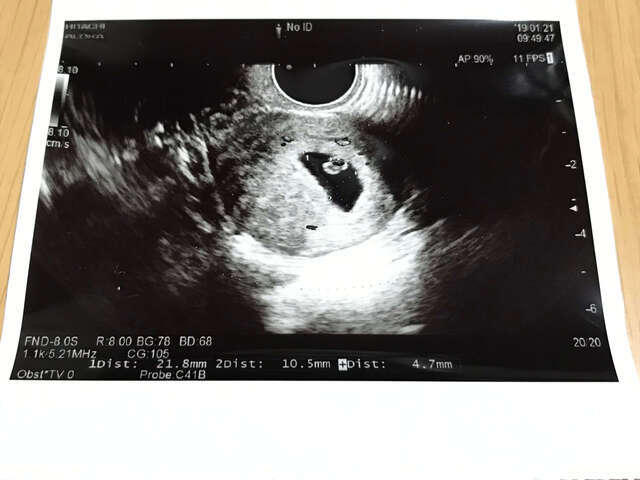

6週4日(6w4d・女の子)|ともゆき さん(39歳)

エコー写真撮影時のエピソード:

妊娠してるかどうか、まだ不確かで、それに加えて、それまでの妊娠が、初期のリングが見えない状態でダメになっていることが続いていたので、不安な時期でのエコー写真。リングが見え、心拍も確認されて、ほっと一安心した日でした。それと同時に、悪阻も始まりだし、仕事もしていたので、しんどい時期でした。